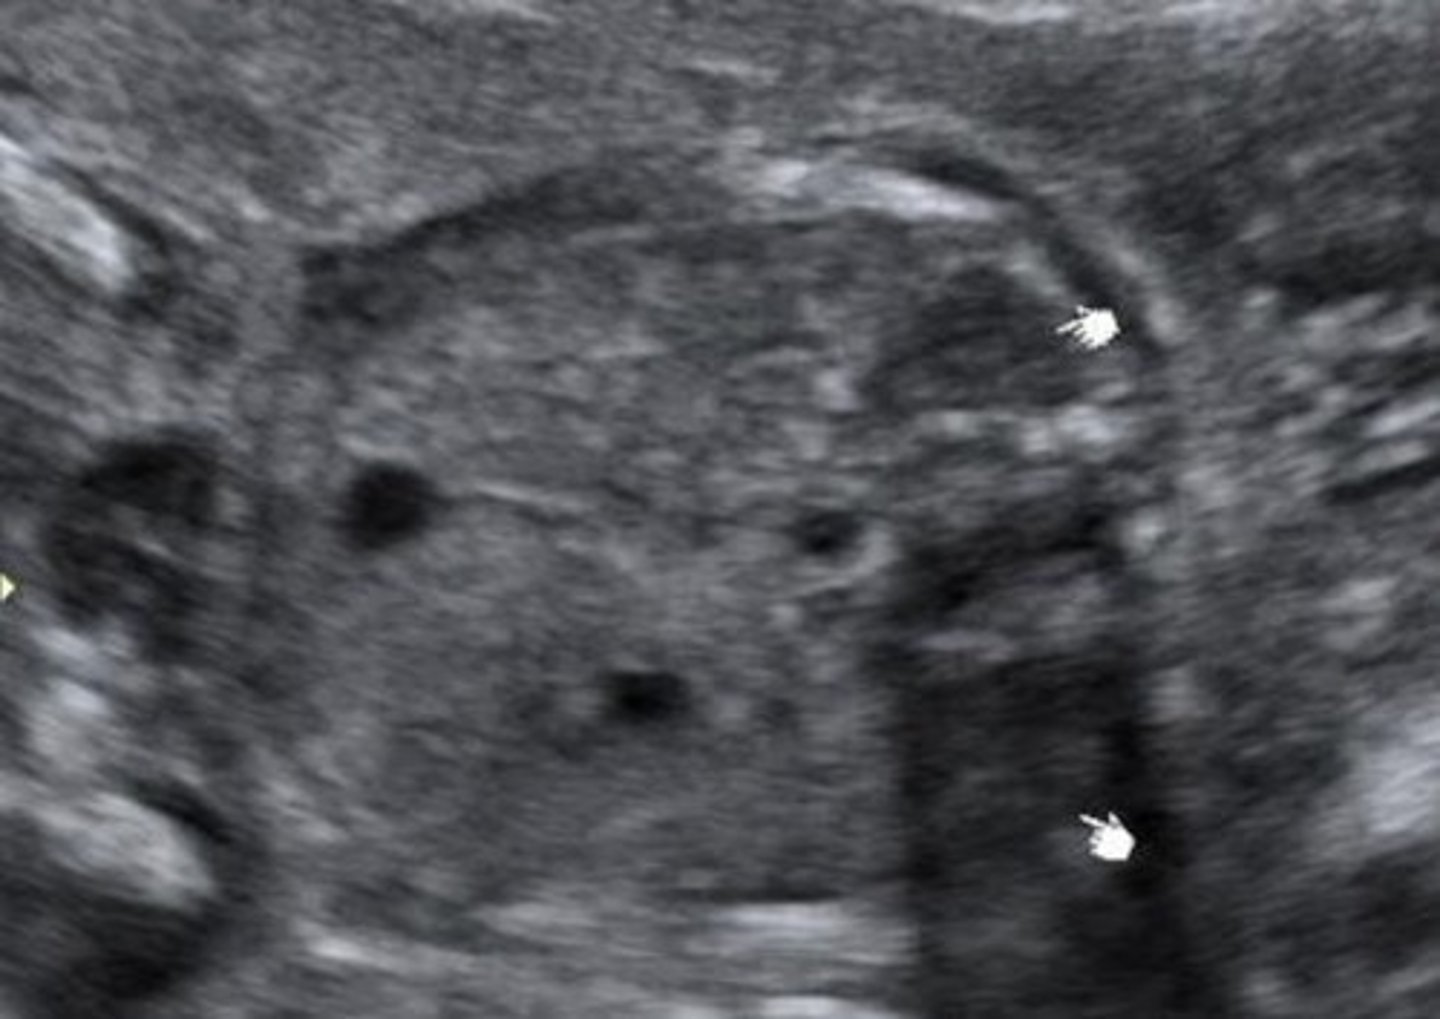

Potter's Syndrome Type II - Multicystic Dysplastic Kidney Disease

Kidney tissue is replaced by cysts - multiple and variable in size

Usually unilateral

Enlarged kidneys

Ill-defined walls & parenchyma/pelvis